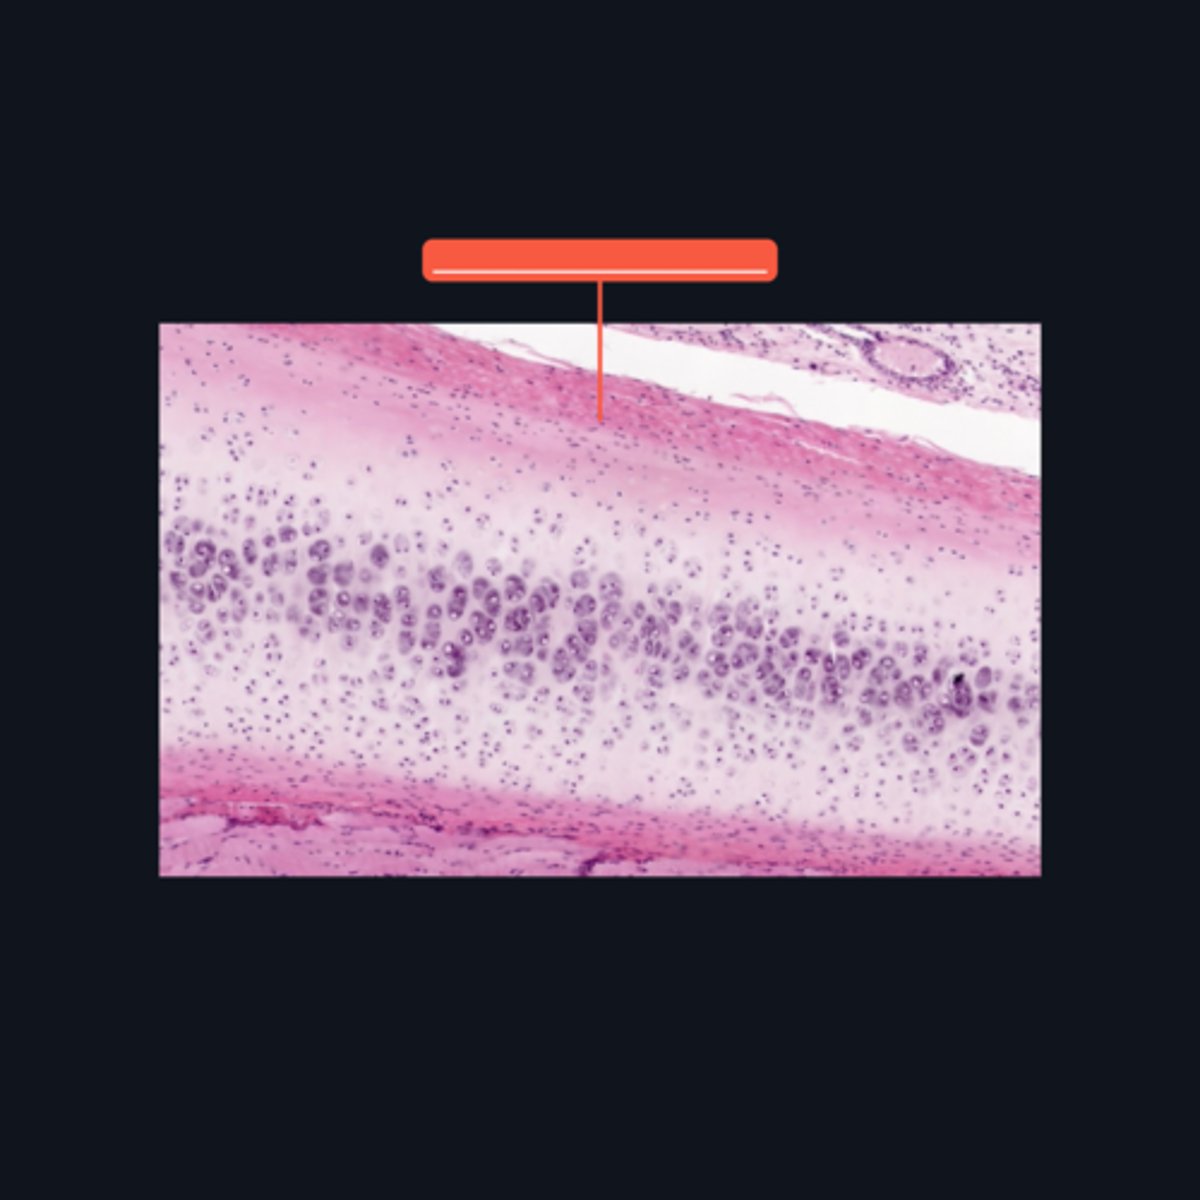

Fibrocartilage; intervertebral disc, articular disc, glenoid and acetabular labra

What type of cartilage is in the image? Where is this specific type of cartilage found?

Collagen fibers

This type of cartilage is abundant in what fibers?

Dense regular connective tissue; chondrocytes; lacunae

This cartilage is commonly mistaken as _____. However, when examined closely, _____are contained in _____ (identify pointed structures), making it a cartilage.